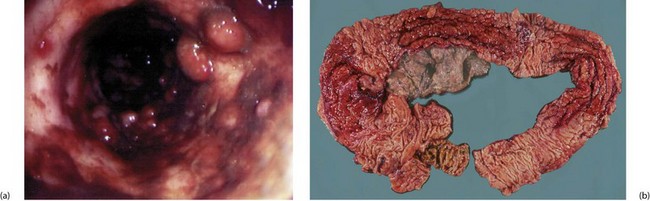

Fig. 28.11 Appearances of Crohn's colitis

(a) This is a typical colonoscopic view of florid Crohn's colitis. Note the nodular appearance producing a ‘cobblestone’ surface with linear ulcers between the nodules. (b) This subtotal colectomy specimen was removed from a man of 54 with a long history of weight loss, diarrhoea and abdominal pain (see barium enema, Fig. 28.10). There are three ‘skip lesions’ typical of Crohn's disease, in the ascending colon, the transverse colon and the hepatic flexure showing thickening of the wall, cobblestone mucosal surface and narrowing of the lumen